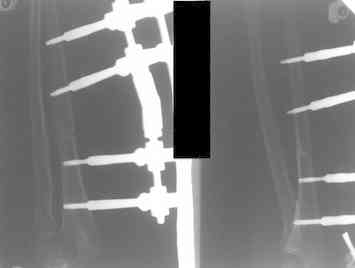

Иллюстрация к лечению застарелого повреждения Монтеджиа

Пациентка клиники детской травматологии ЦИТО

На рентненграмме видна деформация локтевой кости на границе верхней и средней трети. Ведь там был перелом.

Уважаемые коллеги, кто-нибудь еще видит здесь застарелое повреждение Монтеджи? Может мне показалось?

Уважаемый Абдурашид, у ребенка имеется последствие повреждения Монтеджиа. В данном случае в связи деформацией локтевой кости показано двух этпаное лечение. Первым этапом в аппарате Илизарова проводиться низведение головки лучевой кости. Вторым этапом проводится корригирующая остеотомия локтевой кости на границе средней и верхней трети с остеосинтезом либо в аппарате Илизарова, либо стержнем Богданова. Востанавливается нормальная .иогнутая форма локтевой кости. Далее проводится ревизия луче-плечевого сочленения. Иссекаются рубцовые ткани. Головка вправляется и фиксируется спицей на 3-4 недели (либо ллавсановой лентой).

Без коорегирующей остеотомии локтевой кости рецидив вывиха головки лучевой кости неизбежен.